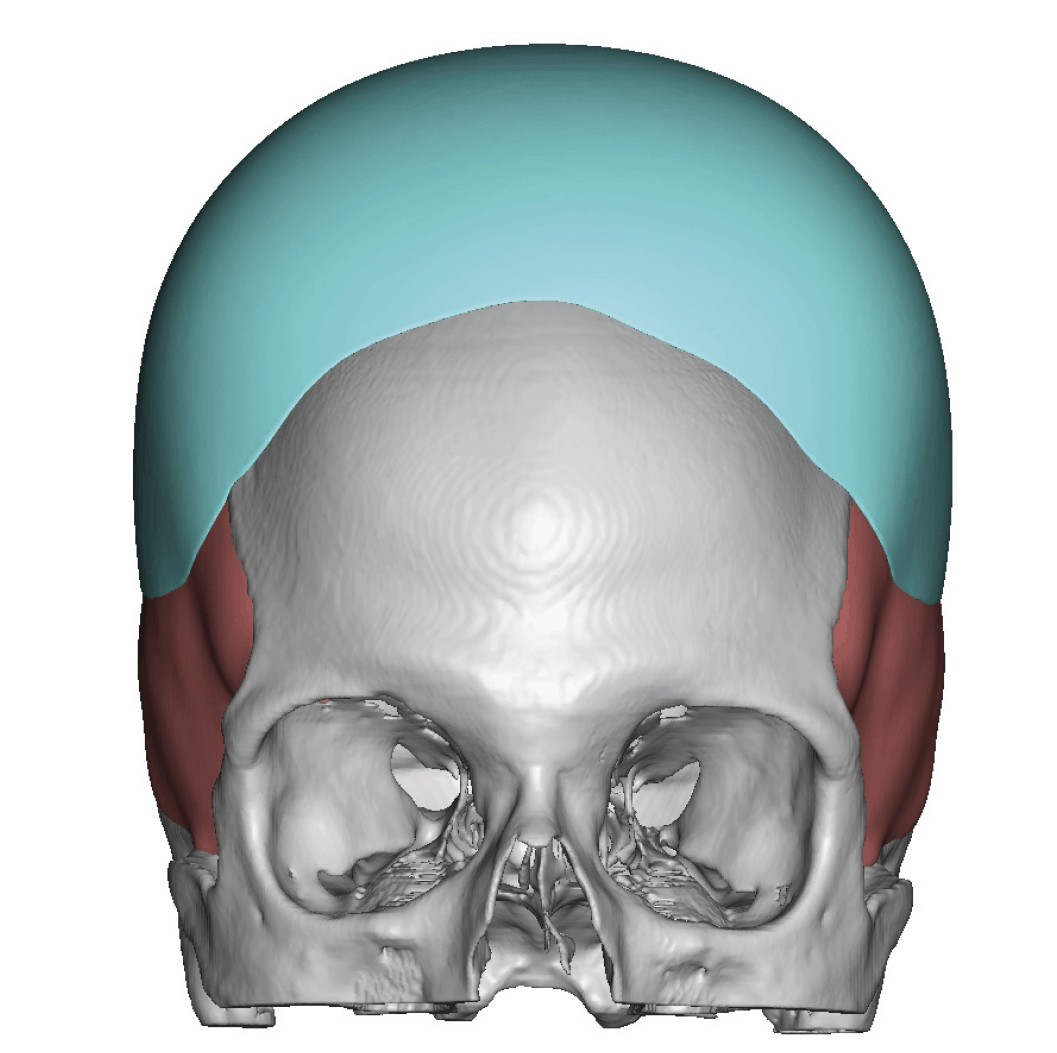

Severe narrowing skull deformity from prior sagittal craniosynostosis repair as an adult.

Complete replacement of entire skull by a custom implant with temporal fat injections.

Severe narrowing skull deformity from prior sagittal craniosynostosis repair as an adult.

Complete replacement of entire skull by a custom implant with temporal fat injections.